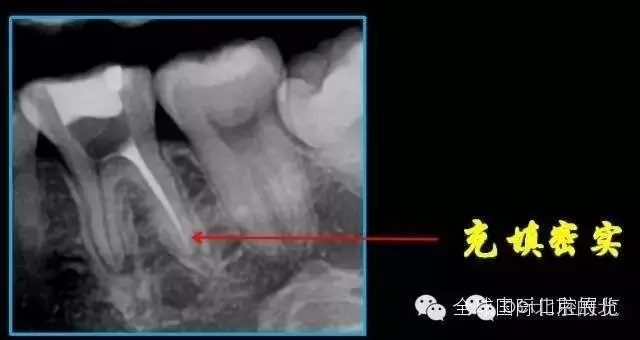

終于找到MB了,然后把根管口MM,ML封閉,S3機(jī)擴(kuò),F(xiàn)1.04錐度牙膠試尖,期盼了好久的柳暗花明終于出現(xiàn)。

終于完成根充

MM,ML其實(shí)融合為一個(gè)根管口的,截面就是三根管的形態(tài),然后做了一個(gè)簡(jiǎn)單清晰的三維重建,形態(tài)還是挺不錯(cuò)的 。